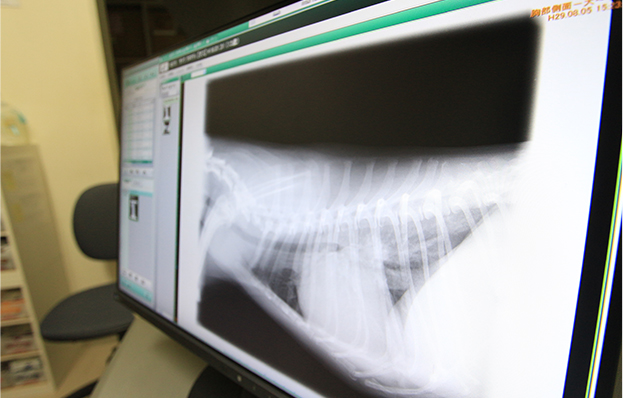

胸部レントゲン検査

心臓・肺・気管などの大きさや、またそれらに異常がないかどうかを、レントゲン撮影を行なって確認します。